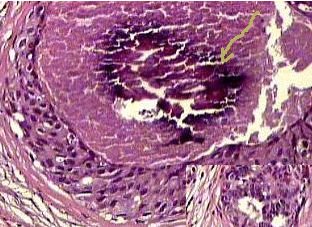

Imagem de uma aula de Anatomia Patológica na qual o professor faz, no momento de sua explicação com voz, uma flexa em uma área que quer apontar.